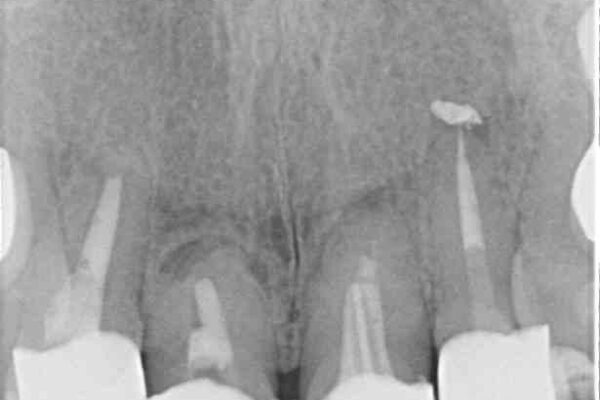

治療前

• 仮歯のまま放置した前歯 オールセラミッククラウンで自然な前歯に 治療前画像